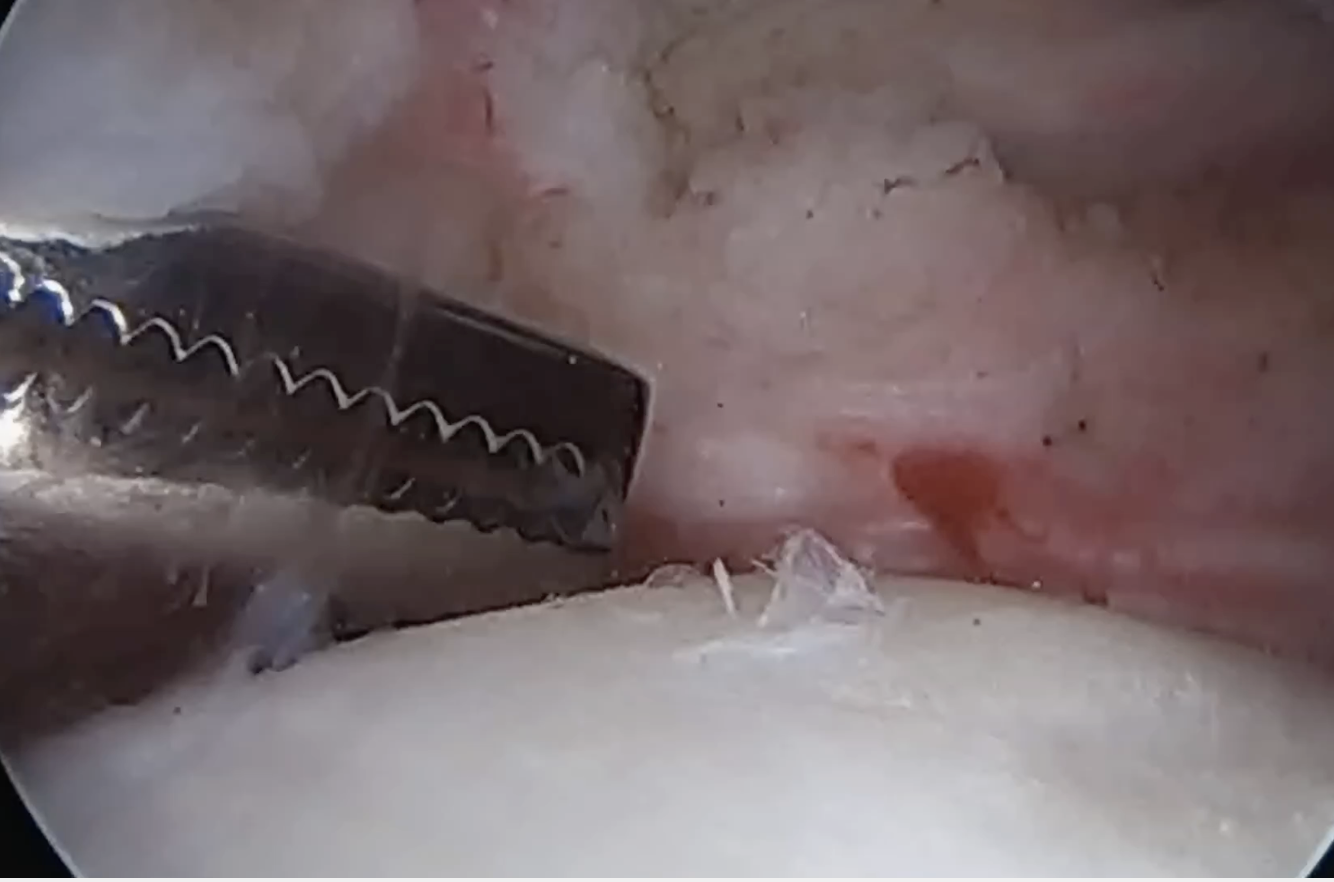

- debride footprint on lesser tuberosity

- insert anchor through anterior portal

Insert anchor through anterior portal into subscapularis footprint